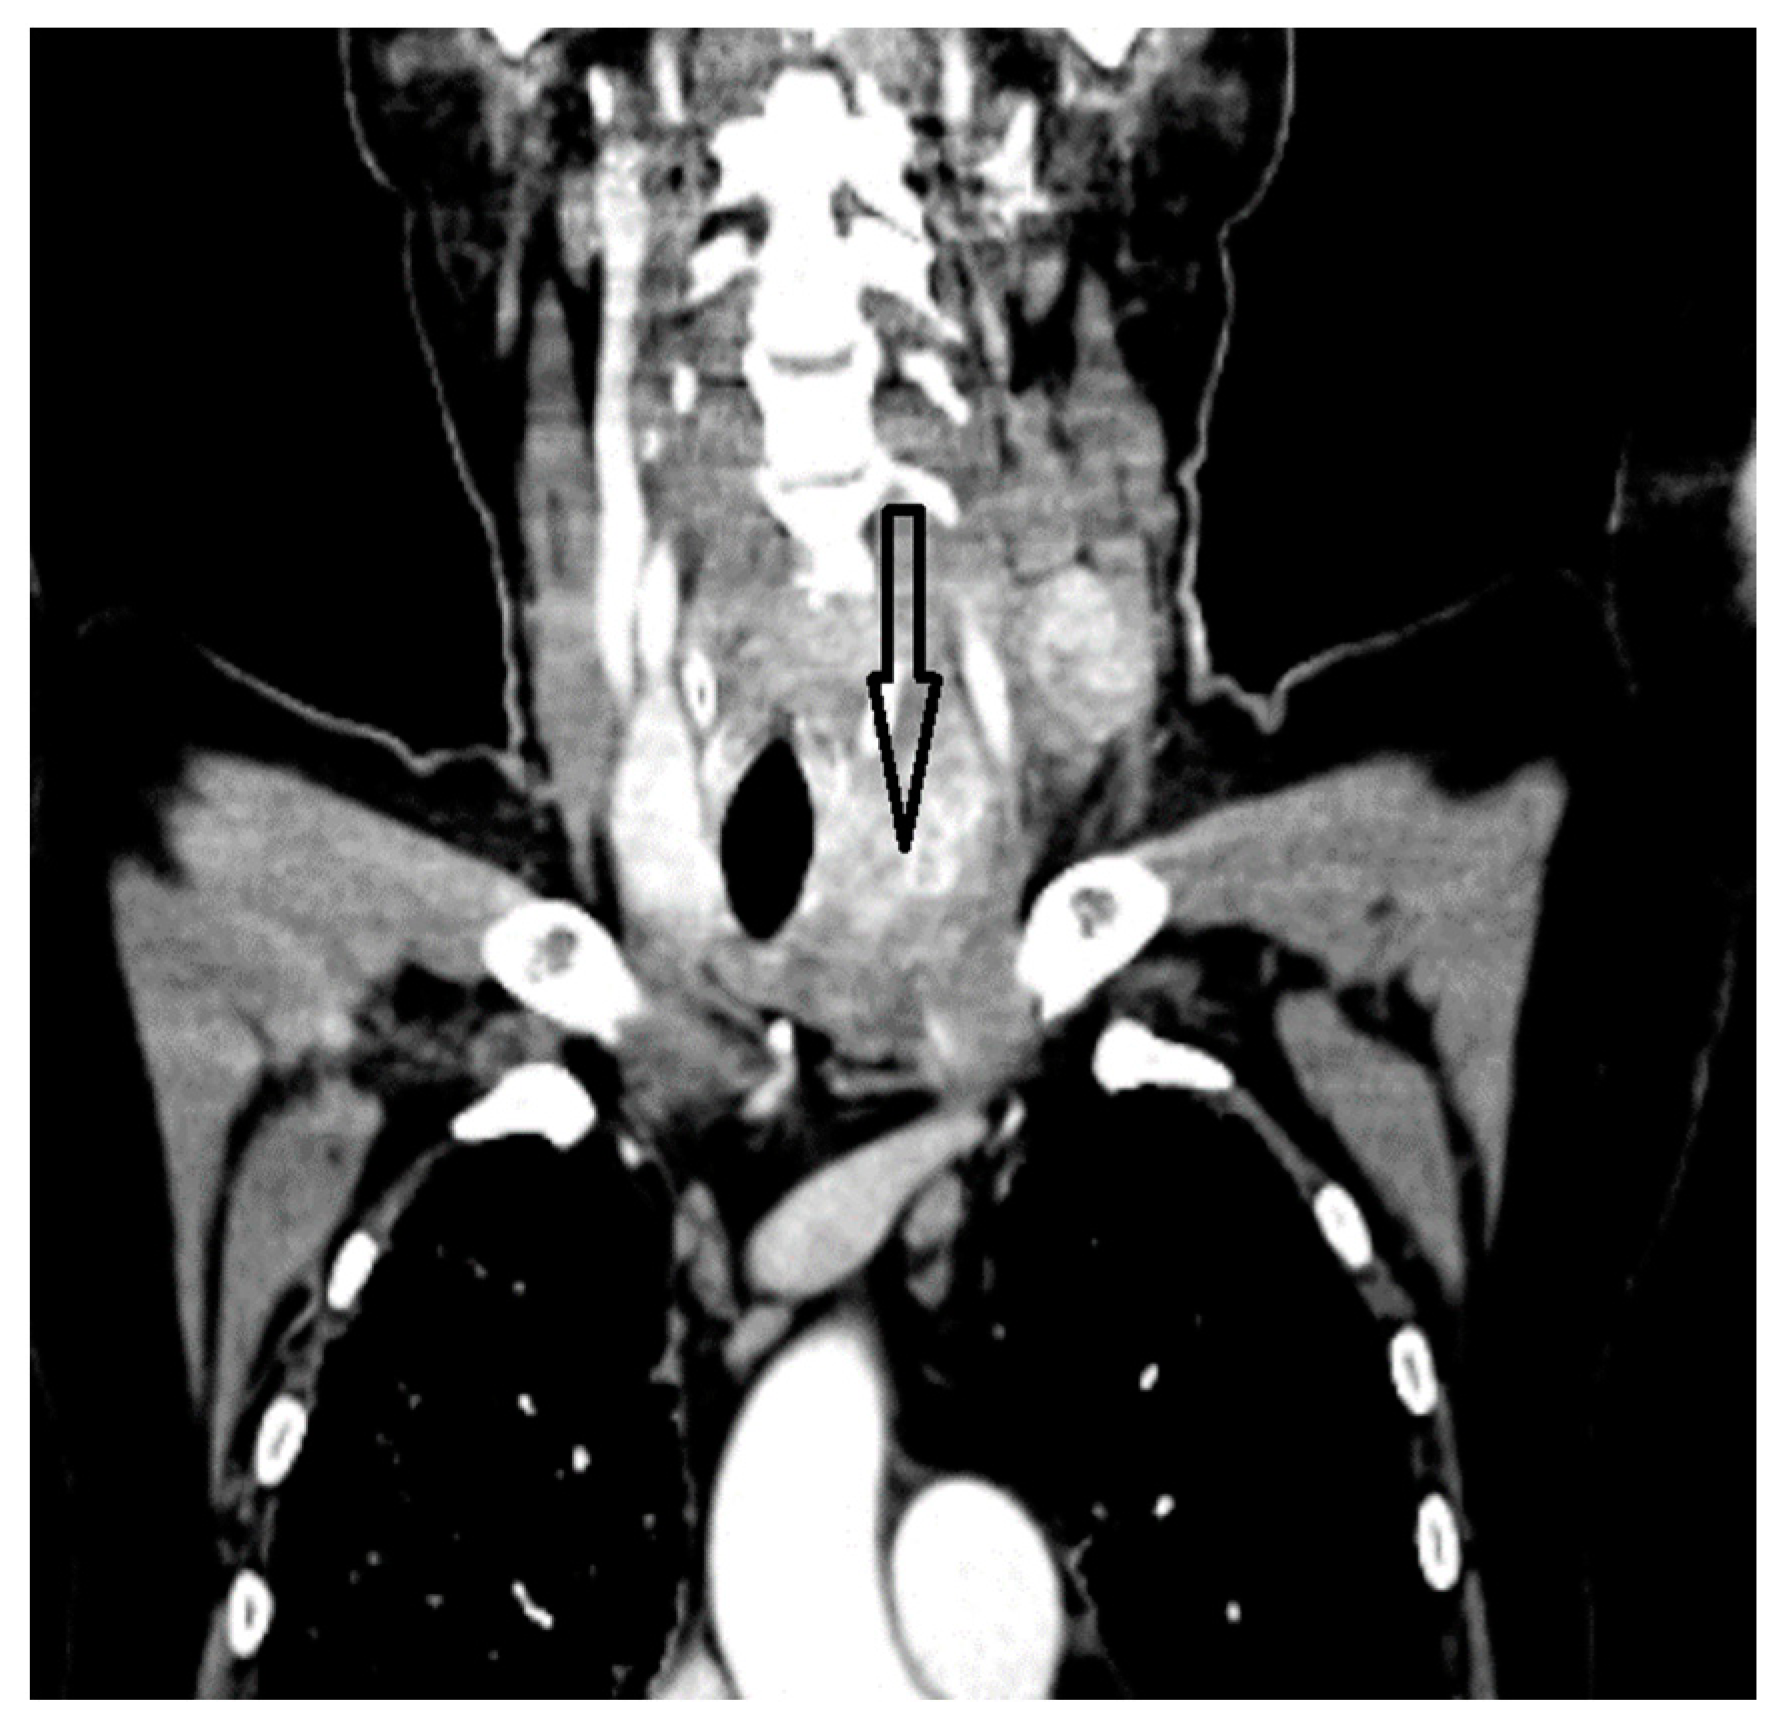

2. Case Report